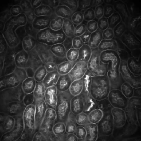

Our proposed method uses this inhomogeneity correction technique as a preprocessing step for both training and inference. Examples of original and inhomogeneity corrected images are shown in Figure 3a and Figure 3b, respectively.

The performance of our proposed method was tested on two different datasets:111 and were provided by Malgorzata Kamocka of the Indiana Center for Biological Microscopy. and . is comprised of grayscale images, each of size pixels, whereas consists of grayscale images, each of size pixels. We selected five different images from and generated corresponding manually annotated groundtruth images to train model . Our deep learning architecture was implemented in Torch [31] using a fixed learning rate and a momentum of . As indicated, pairs of images were generated by the elastic deformation, rotations, and flips using these five pairs of images. Note that each training data was used as a batch so that iterations were performed per epoch. We used epochs for training our proposed network. In addition, was used for the removal of small objects. The performance of the proposed method was evaluated using manually annotated groundtruth images () at different depths in that were never used during the training stage. For visual evaluation and comparison segmentation results of in using various techniques are presented in Figure 3.

The first row in Figure 3 displays an original microscopy image (), its inhomogeneity corrected version (), and manually delineated groundtruth (), respectively. For brevity we have omitted the superscript in the notation. The second row shows segmentation results of various 3D methods such as 3D region-based active contours [10] (3Dac), 3D active contours with inhomogeneity correction [11] (3DacIC), and 3D Squassh presented in [12] (3Dsquassh). Similarly, the third row portrays various segmentation methods particularly designed for tubular structure segmentation such as ellipse fitting method presented in [15] (Ellipse Fitting), the Jelly filling method in [20] (Jelly Filling), and tubule segmentation using steerable filter [21] (Steerable Filter). Finally, the last row shows segmentation results of our proposed CNN architecture without inhomogeneity correction [27] (2DCNN) and with inhomogeneity correction (2DCNNIC).

For visual comparison we highlighted groundtruth regions in red, segmented tubule regions in green, and background in black. As observed in Figure 3, our proposed method appeared to perform better than the other six methods shown in the second and third rows by distinguishing tubules and was similar performance to 2DCNN. Note that since some methods such as Ellipse Fitting, Jelly Filling, and Steerable Filter only segmented boundaries of tubule structures, tubule interiors were filled in order to perform a fair comparison using connected components with a -neighborhood systems. Also, based on the assumption that tubule regions should contain lumen, if a filled region contained lumen pixel, the region was identified as a tubule region. However, if a filled region did not contain any lumen pixels, the region was considered as a background region.

The segmentation results shown in the second row generally missed many tubule regions. More specifically, 3Dac and 3Dsquassh could not capture the tubular structures but captured some in the center regions due to the intensity inhomogeneity of microscopy images. 3DacIC failed to segment tubular structures but captured multiple lumens inside tubules as well as some tubule boundaries. In contrast, the segmentation results displayed in the third row showed falsely detected tubules. The main reason is that these tubule segmentation methods focused only on detecting boundaries of tubular structures. In particular, due to weak/blurry edges of fluorescence microscopy images, many boundaries were not continuous causing the filling operation to overflow from one tubule to another or to the background regions. The segmentation results using the CNN generally successfully segmented and identified each tubule region.

Figure 4 provides an alternative way to show the segmentation results. In particular, yellow regions correspond to true positives which are pixel locations that are identified as tubules in both the groundtruth and segmentation results. Green regions correspond to false positives which are pixel locations that are identified as background in groundtruth but tubules in segmentation results. Similarly, red pixels correspond to false negatives, namely pixel locations identified as tubules in the groundtruth but background in segmentation results, and black pixel regions correspond to true negative that are identified as background in both groundtruth and segmentation results. The green regions indicate Type-I error (false alarm) regions and the red regions represent Type-II error (miss) regions. As observed from Figure 4, the segmentation results in the first row contained large red regions which mean large regions of tubules were missed. Conversely, the segmentation results shown in the second row contained many green regions indicating many background regions were falsely segmented as tubule regions. In contrast, the segmentation results in the third row had reasonably small green regions and red regions which indicate that the deep learning based segmentation results had higher pixel accuracy with relatively low Type-I and Type-II errors.